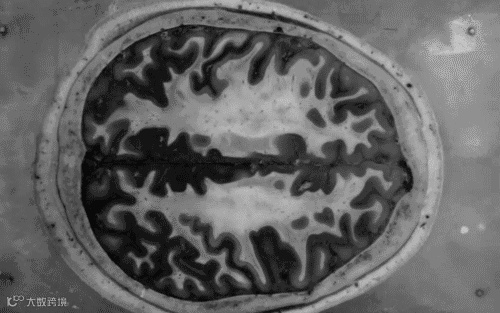

大脑对于人类来说,还有太多未知等待探索,脑部疾病的治疗一直以来都是人类面临的巨大难题。被称为“沉默杀手”的帕金森病 (Parkinson’s disease),是中老年人群中较为常见的神经性疾病,其主要症状有动作迟缓, 身体僵硬, 静止时震颤和拖步曳行等。人们对帕金森并不陌生,全球约有700万至1000万人受帕金森的影响,其中包括国际巨星迈克尔.福克斯和拳王阿里等名人。

干细胞科技的发展给我们带来了巨大的希望,临床研究发现,干细胞治疗对大脑及脑部神经都有明显的修复作用。

目前,clinicaltrials.gov上登记在案的干细胞治疗脑部疾病(包括帕金森、中风)的临床实验超过400例,相信随着科学家们的不断努力,干细胞能够为更多的脑部疾病患者带来福音。每年4月11日是世界帕金森日,小编整理一些关于干细胞治疗脑科部疾病的一些进展,仅供参考。